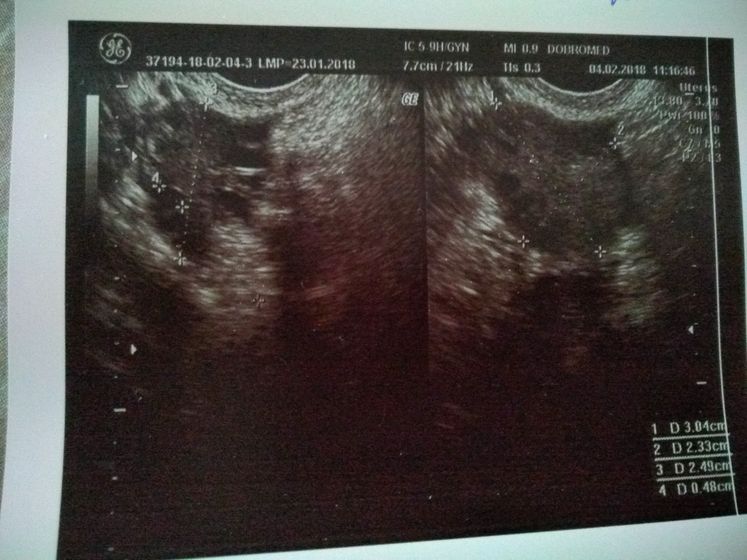

Поехали сегодня в пургу и вьюгу на УЗИ в Добромед(не в восторге) Сделали узи, рассказала что и как врачу, при осмотре было желтое тело, но как я поняла, не совсем то что нужно. В остальном все хорошо, матка, яичники все в норме. Критичного ни чего нет. Послали на ХГЧ завтра за результатом. Если есть, кто разбирается в заключении и в узи, буду рада информации. Тест все еще показывает //